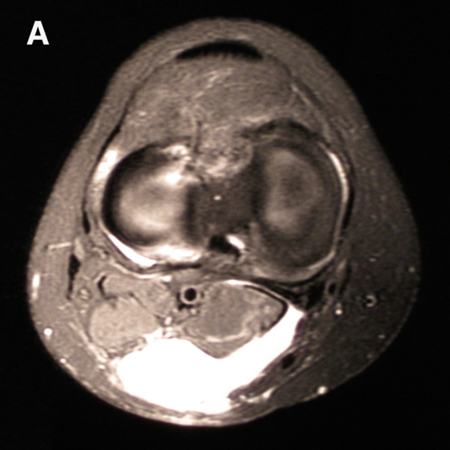

One study demonstrated that popliteal cysts develop from lack of external anatomical support.[1] This area is found between the two expansions of the semimembranosus muscle and the medial gastrocnemius.[Figure caption and citation for the preceding image starts]: MRI depicting cyst in interval of medial gastrocnemius and semimembranosusFrom the collection of Dr John D. Kelly IV; used with permission [Citation ends].